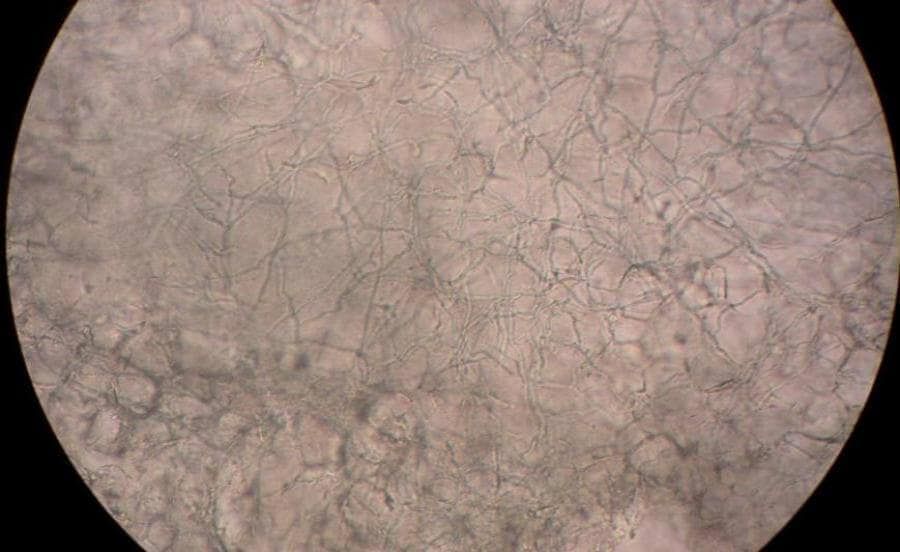

Tinea infections are caused by dermatophytes and are classified by the involved site. The most common infections in prepubertal children are tinea corporis and tinea capitis, whereas adolescents and adults are more likely to develop tinea cruris, tinea pedis, and tinea unguium (onychomycosis). The clinical diagnosis can be unreliable because tinea infections have many mimics, which can manifest identical lesions. For example, tinea corporis can be confused with eczema, tinea capitis can be confused with alopecia areata, and onychomycosis can be confused with dystrophic toe-nails from repeated low-level trauma. Physicians should confirm suspected onychomycosis and tinea capitis with a potassium hydroxide preparation or culture. Tinea corporis, tinea cruris, and tinea pedis generally respond to inexpensive topical agents such as terbinafine cream or butenafine cream, but oral antifungal agents may be indicated for extensive disease, failed topical treatment, immunocompromised patients, or severe moccasin-type tinea pedis. Oral terbinafine is first-line therapy for tinea capitis and onychomycosis because of its tolerability, high cure rate, and low cost. However, kerion should be treated with griseofulvin unless Trichophyton has been documented as the pathogen. Failure to treat kerion promptly can lead to scarring and permanent hair loss.